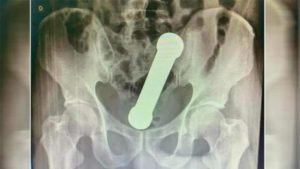

La radiografía reveló que una mancuerna, de unos 20 cm, estaba alojada entre el colon y el recto del hombre.